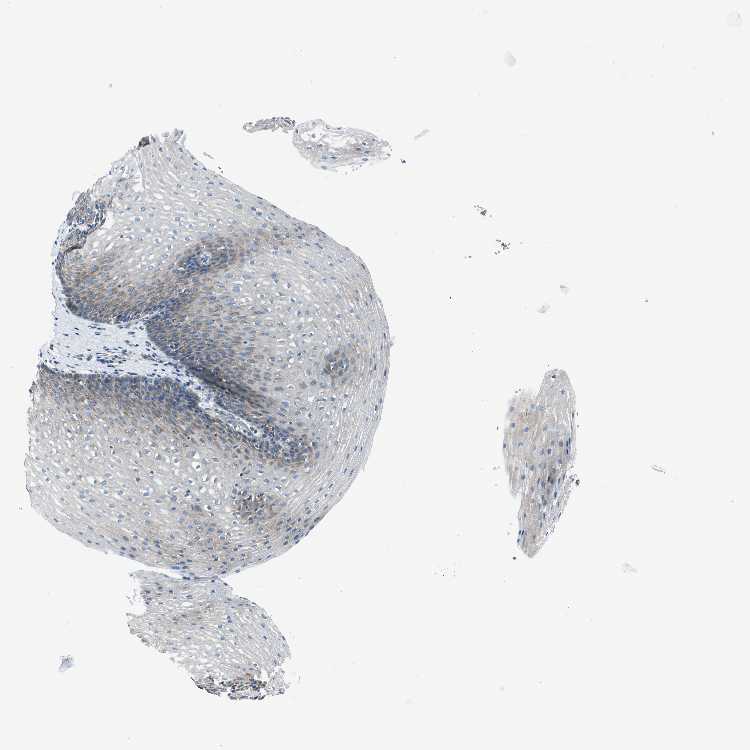

ESOPHAGUS - Antibody stainingi

Antibody staining in the annotated cell types in the current human tissue is reported as not detected, low, medium, or high, based on conventional immunohistochemistry profiling in selected tissues. This score is based on the combination of the staining intensity and fraction of stained cells.

Each image is clickable and will lead to virtual microscopy that enables deeper exploration of all samples and also displays staining intensity scores, fraction scores and subcellular localization as well as patient and tissue information for each sample.

Antibody HPA016939Antibody HPA064668

Squamous epithelial cells LowMedium